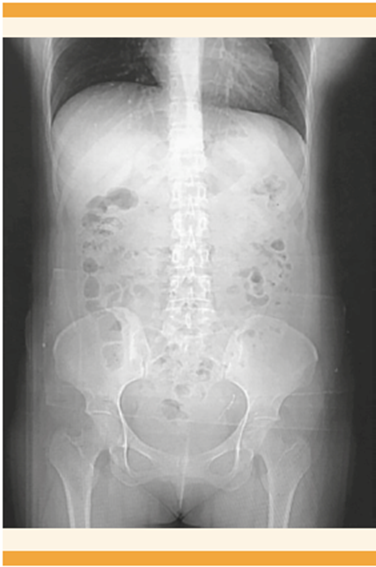

Acudió a la consulta externa de Ginecología debido a un dolor pélvico 7-10 en la escala visual análoga del dolor (EVA), con sangrados menstruales regulares aumentados en volumen y dos intentos fallidos de extracción del DIU en un consultorio. En la exploración física el abdomen se palpó blando, depresible, doloroso a la palpación profunda, el útero no delimitado, sin masas palpables. En la especuloscopia no se observaron los hilos del DIU, sin huellas de sangrado. El estado hemodinámico de la paciente era estable, sin datos de irritación peritoneal. La radiografía abdominopélvica anteroposterior evidenció el DIU en el hueco pélvico izquierdo (Figura 1). El ultrasonido endovaginal el útero se observó en retroflexión de 68 x 37 x 47 mm. El endometrio trilaminar, los anexos derechos normales, al igual que el ovario izquierdo. El fondo de saco sin datos de líquido libre (Figura 2). Para precisar la ubicación del dispositivo se practicó la histeroscopia de consultorio en la que se visualizó el área de granulación en la cara anterior derecha, probable falsa vía. Se corroboró la ausencia del DIU en la cavidad (Figura 3). La TAC simple y contrastada reportó al útero inclinado hacia la izquierda, con el dispositivo intrauterino en la trompa uterina izquierda. Figura 4

Figura 4 TAC abdominopélvica simple y contrastada en donde se localiza el DIU en la trompa uterina izquierda.

El diagnóstico se basa, sobre todo, en la anamnesis, identificación de factores de riesgo, exploración física y pruebas complementarias. La ecografía debe ser el estudio de imagen inicial. 12 La radiografía convencional es útil para el diagnóstico de expulsión o perforación uterina. La TAC ayuda a medir la gravedad de la perforación y evaluar otras complicaciones (secuelas de adherencias, obstrucción intestinal, perforación de estructuras adyacentes, abscesos). 13 En la paciente del caso, el DIU se detectó en la radiografía abdominopélvica; en la TAC en el hueco pélvico, aunque de ubicación imprecisa. Por último, mediante la histeroscopia se corroboró la ausencia del dispositivo en la cavidad, con alta sospecha de perforación uterina.